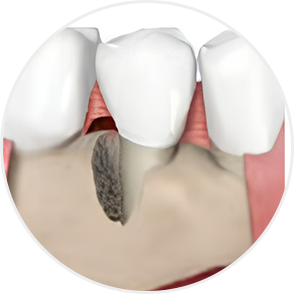

Even when severe periodontal disease has caused gingival recession and alveolar bone resorption, teeth can often be preserved through gum regeneration therapy using Emdogain. This procedure regenerates damaged alveolar bone and surrounding periodontal tissue. By applying Emdogain — a specialized gel that stimulates periodontal tissue regeneration — the supporting structures of the tooth are rebuilt, allowing function and health to be restored without extraction.

Acts deep within the periodontal tissues to support regeneration of the gingiva, periodontal ligament, and alveolar bone around the tooth root.